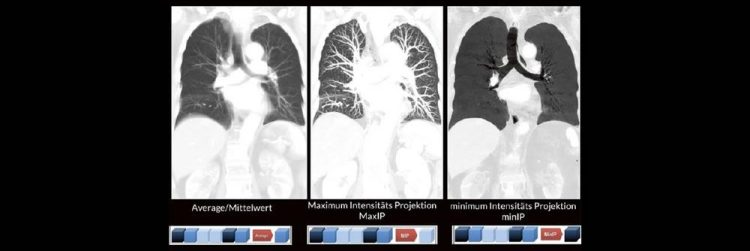

Bildnachverarbeitung in der CT (Webinar | Online)

Alex Riemer Moderne CT-Scanner unterstützen die Anwenderinnen und Anwender bei der Durchführung der meisten CT-Untersuchungen. Hierzu zählt auch das automatische Erstellen von streng coronalen und sagittalen Multiplanaren Reformatierungen (MPR´s).  Es gibt jedoch CT-Untersuchungen, bei denen die MPR´s individuell an die Anatomie angepasst werden müssen. Doch gerade bei diesen Bildnachverarbeitungen gibt es oft Unsicherheiten darüber, worauf…Continue reading Bildnachverarbeitung in der CT (Webinar | Online)